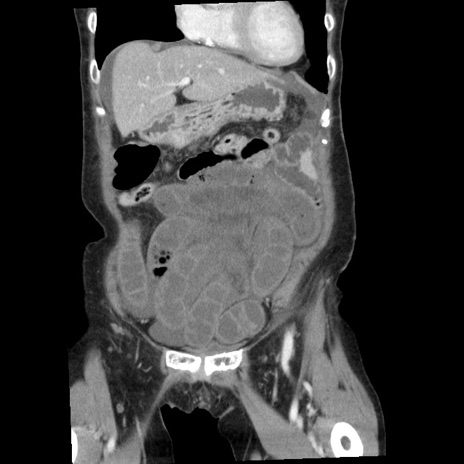

症例1(冠状断像)

【症例】80歳代女性

【主訴】腹痛

【現病歴】8時間前から腹痛あり来院。

【既往歴】糖尿病、脂質異常症、子宮体癌にて子宮全摘術

【身体所見】意識清明・会話良好だが腹痛で苦悶様、全腹部にわたって反跳痛と圧痛あり

【データ】WBC 13600、CRP 0.14、LDH 224、CK 90